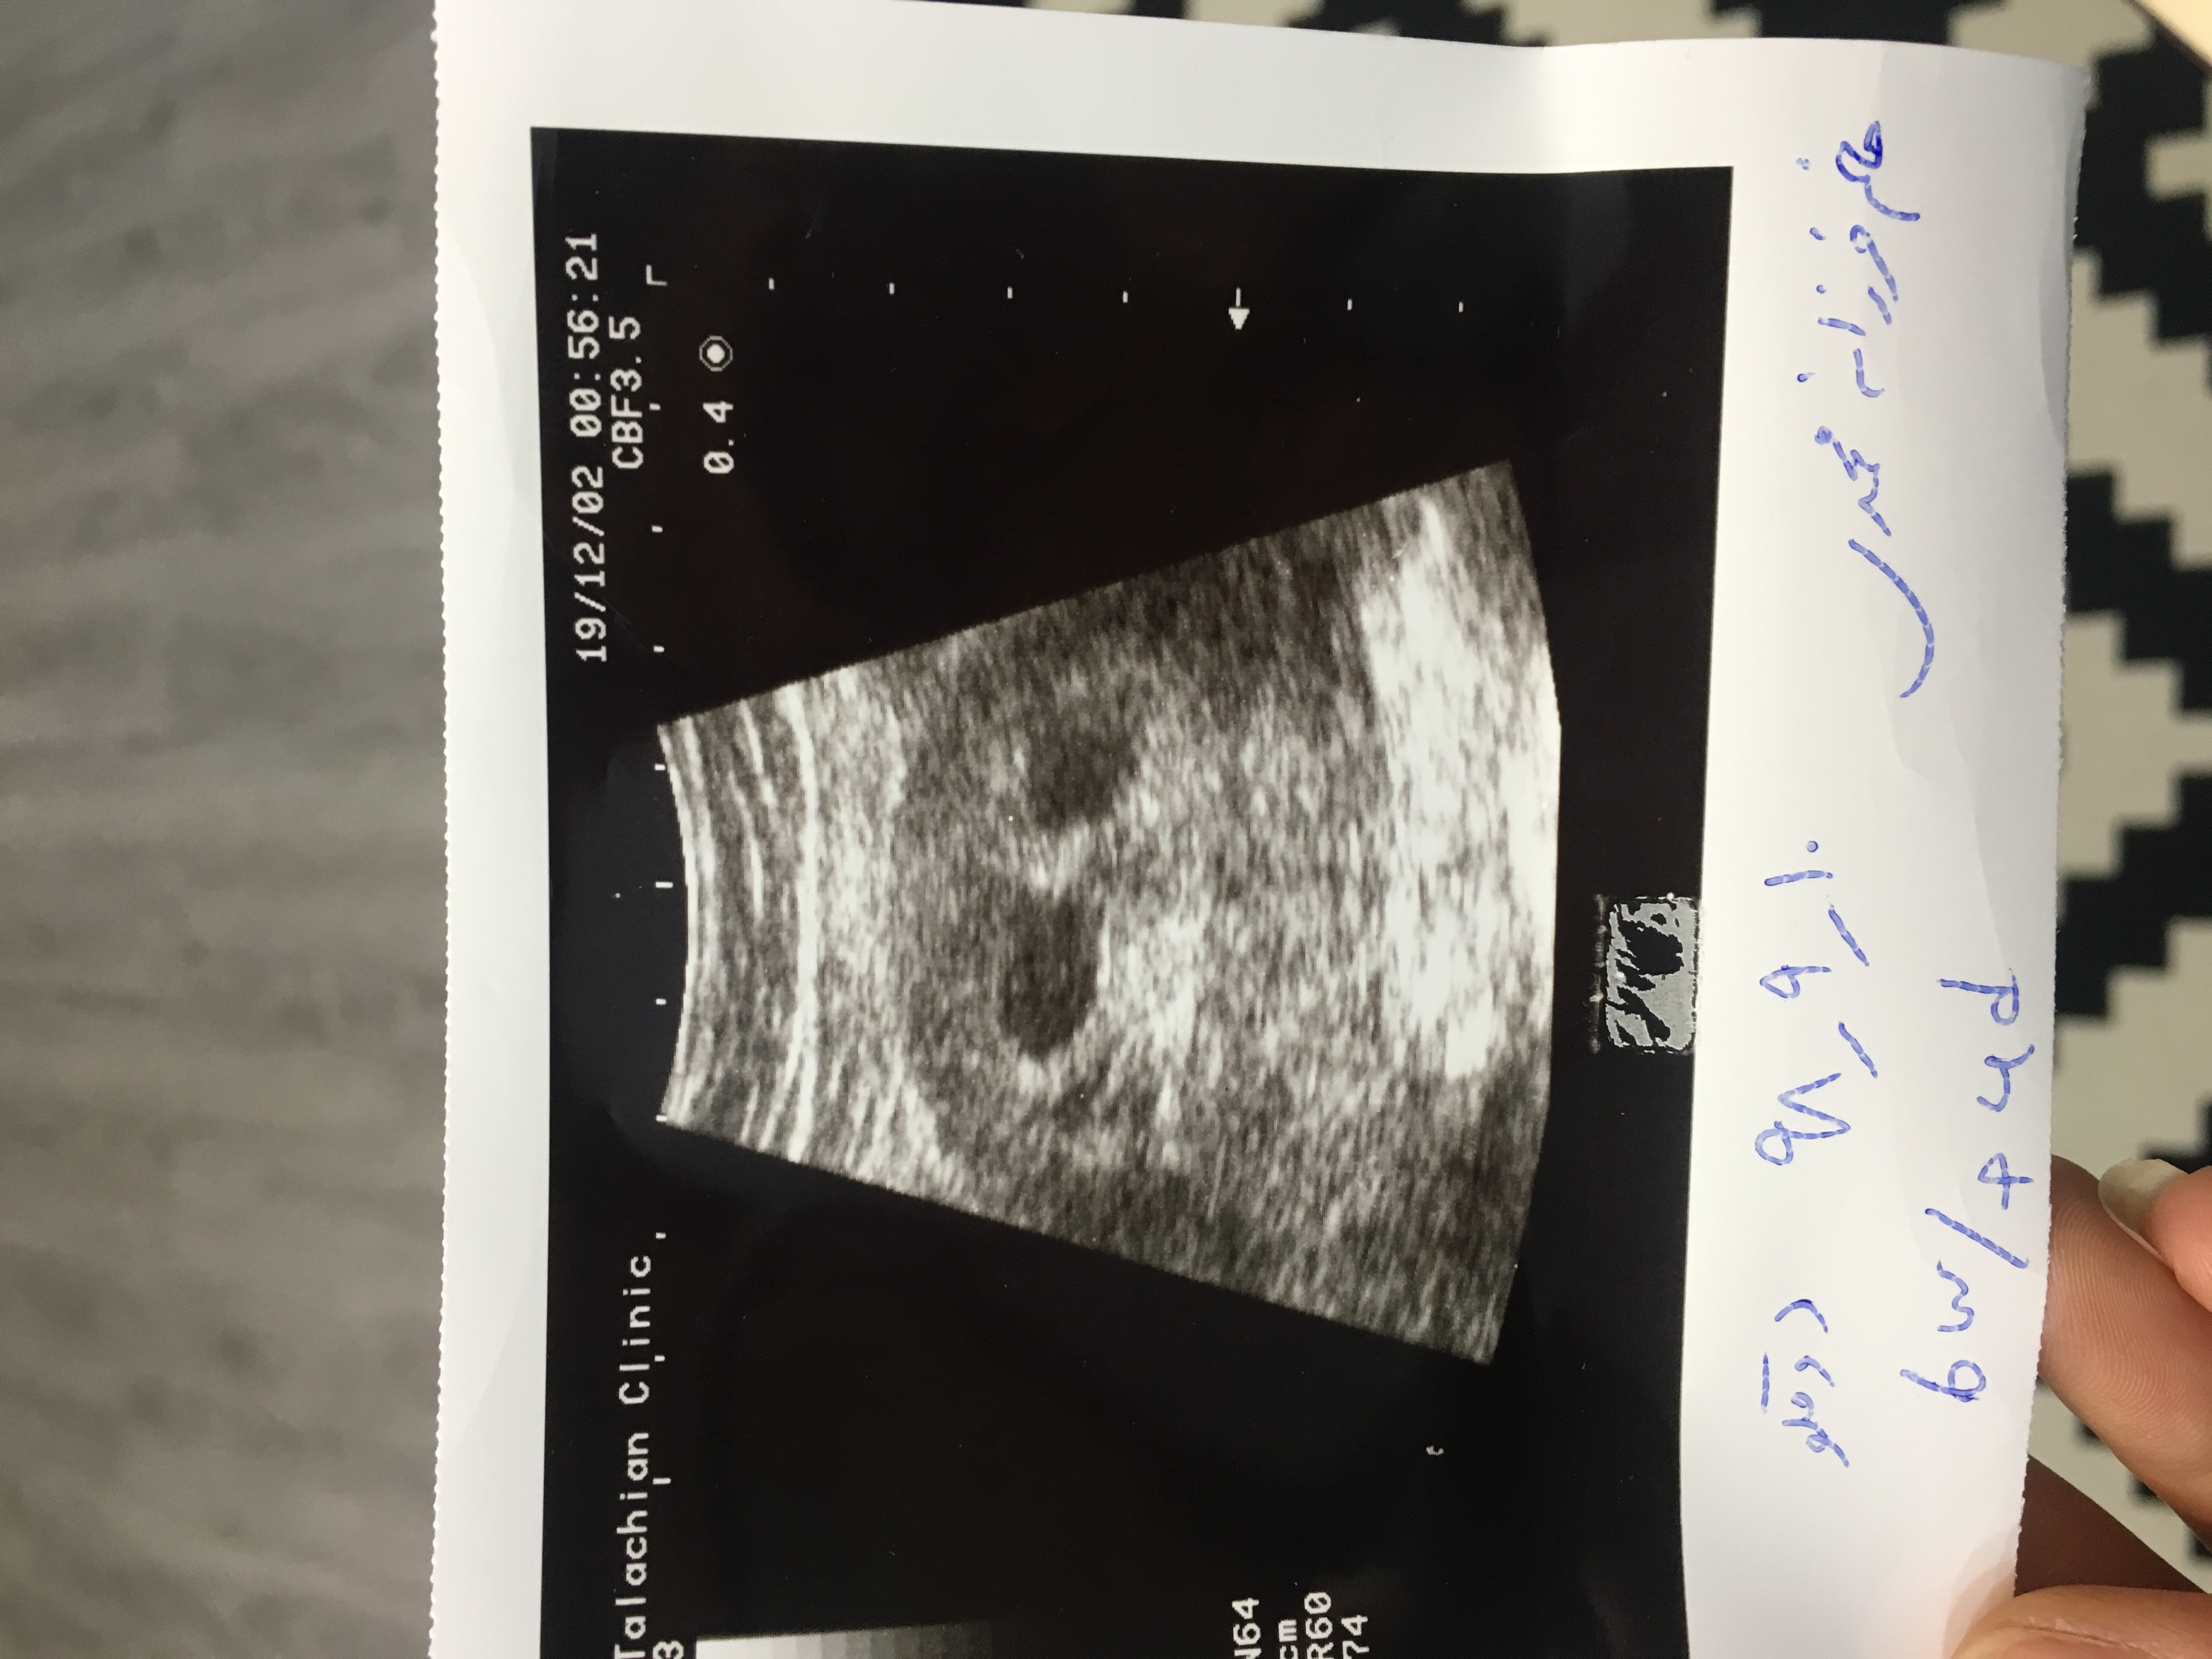

اين عكس اولين سونوي منه،شما متوجه ميشيد همسان هست يا غير همسان؟؟؟شما طبيعي دوقلو باردار شدين يا نه؟